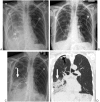

Infectious, traumatic, or neoplastic processes in the chest often result in fluid collections within the pleural, parenchymal, or mediastinal spaces. The same fundamental principles that guide drainages of the abdomen can be applied to the chest. This review discusses various pathologic conditions of the thorax that can result in the abnormal accumulation of fluid or air, and their management using image-guided methods.